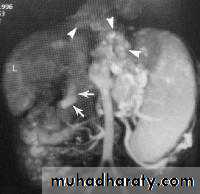

LEFT: Dilated esophagus (arrows) appears as long, well-defined structure paralleling heart RIGHT: Dilated esophagus usually deviates to right. Narrowing (arrow) at hiatus.

LEFT: CT shows dilated esophagus (arrow) that led to esophagram.RIGHT: Esophagram shows narrowing (arrow) at level of hiatus.